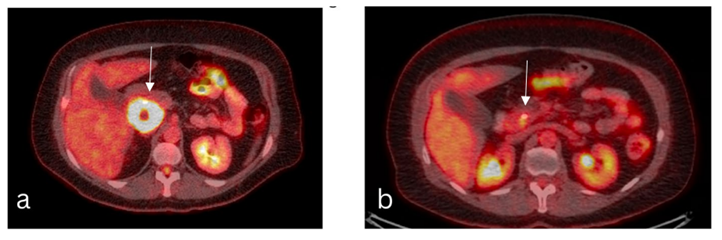

A PET scan done in July 2021, approximately 6 weeks after the end of radiation therapy, showed a markedly decreased pancreatic lymphoma mass with residual small focus on FGD uptake slightly above liver activity, when compared to pet scan done on 04/16/2021. This focus was covered by the higher radiation dose (50Gy) and it was considered to be most likely inflammatory. No other FGD avid lesions were seen (figure 3a and 3b).

Figure 3: (a)-PET/CT simulation: 04/16/2021. Reference regions: SUVmax and mean in a reference region in the liver are 2.4 and 1.9. Pancreas: FDG avid pancreatic head mass (5.6x 5.1 cm, SUV 28.8) with central hypodensity/photopenia, possibly cystic/necrotic change or ductal dilatation. (b)-PET: 07/14/2021. Reference regions: SUVmax and mean in a reference region in the liver are 2.8 and 1.9. Pancreas: Markedly decreased size and FDG uptake of pancreatic head mass with ill-defined residual focal FDG uptake adjacent to the biliary stent, image 165, SUV 4.8, previously 5.6x5.1 cm, SUV 28.8; Images from our institutional radiology department.